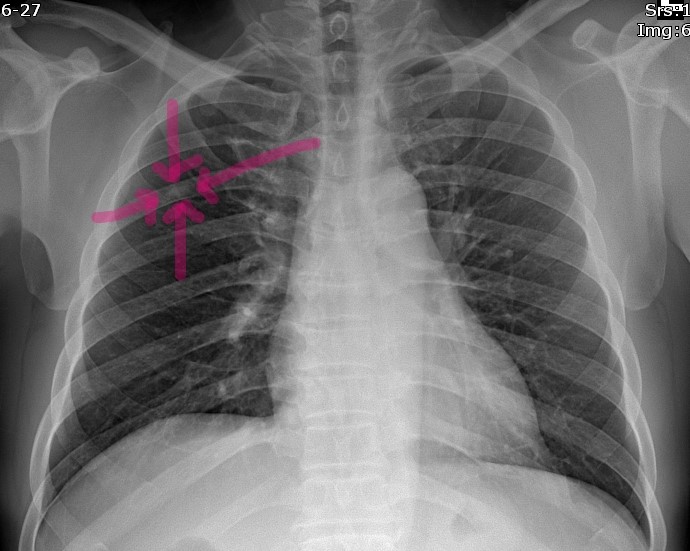

Spotted Bone A Spot Diagnosis British Journal of Medical Practitioners

From www.bjmp.org

Spotted Bone A Spot Diagnosis British Journal of Medical Practitioners What Is A Bone Island In The Neck enostosis, also known as bone island (bi), is a common benign osseous lesion that consists of a focus of compact. a bone island is cortical bone found along the surface of the bone located within the shaft or central cavity of the bone. bone island, also known as enostosis, is a benign bone lesion commonly found on. What Is A Bone Island In The Neck.